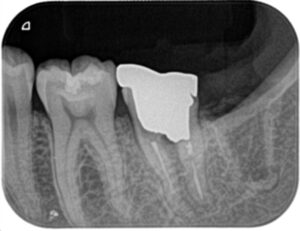

レントゲン撮影を行うと、近心および分岐部に影が映りました。ここは歯に穴(穿孔)が開いており、そこから細菌感染して歯の周りの骨が溶けてしまっています。

被せ物および土台を除去すると肉芽が増殖しており、電気メスで除去。MTAセメントで穴を塞ぎました。

穿孔修復を行った後は痛みが落ち着いたため、根管内の古いガッタパーチャーを除去し、十分に次亜塩素酸ナトリウム水溶液(通称ヒポクロ)で洗浄した後根管充填を行いました。

近心および分岐部の穿孔修復ならびに根尖が壊れていた遠心根をMTAで充填しました。

(近心根は通常のガッタパーチャーで充填してます)